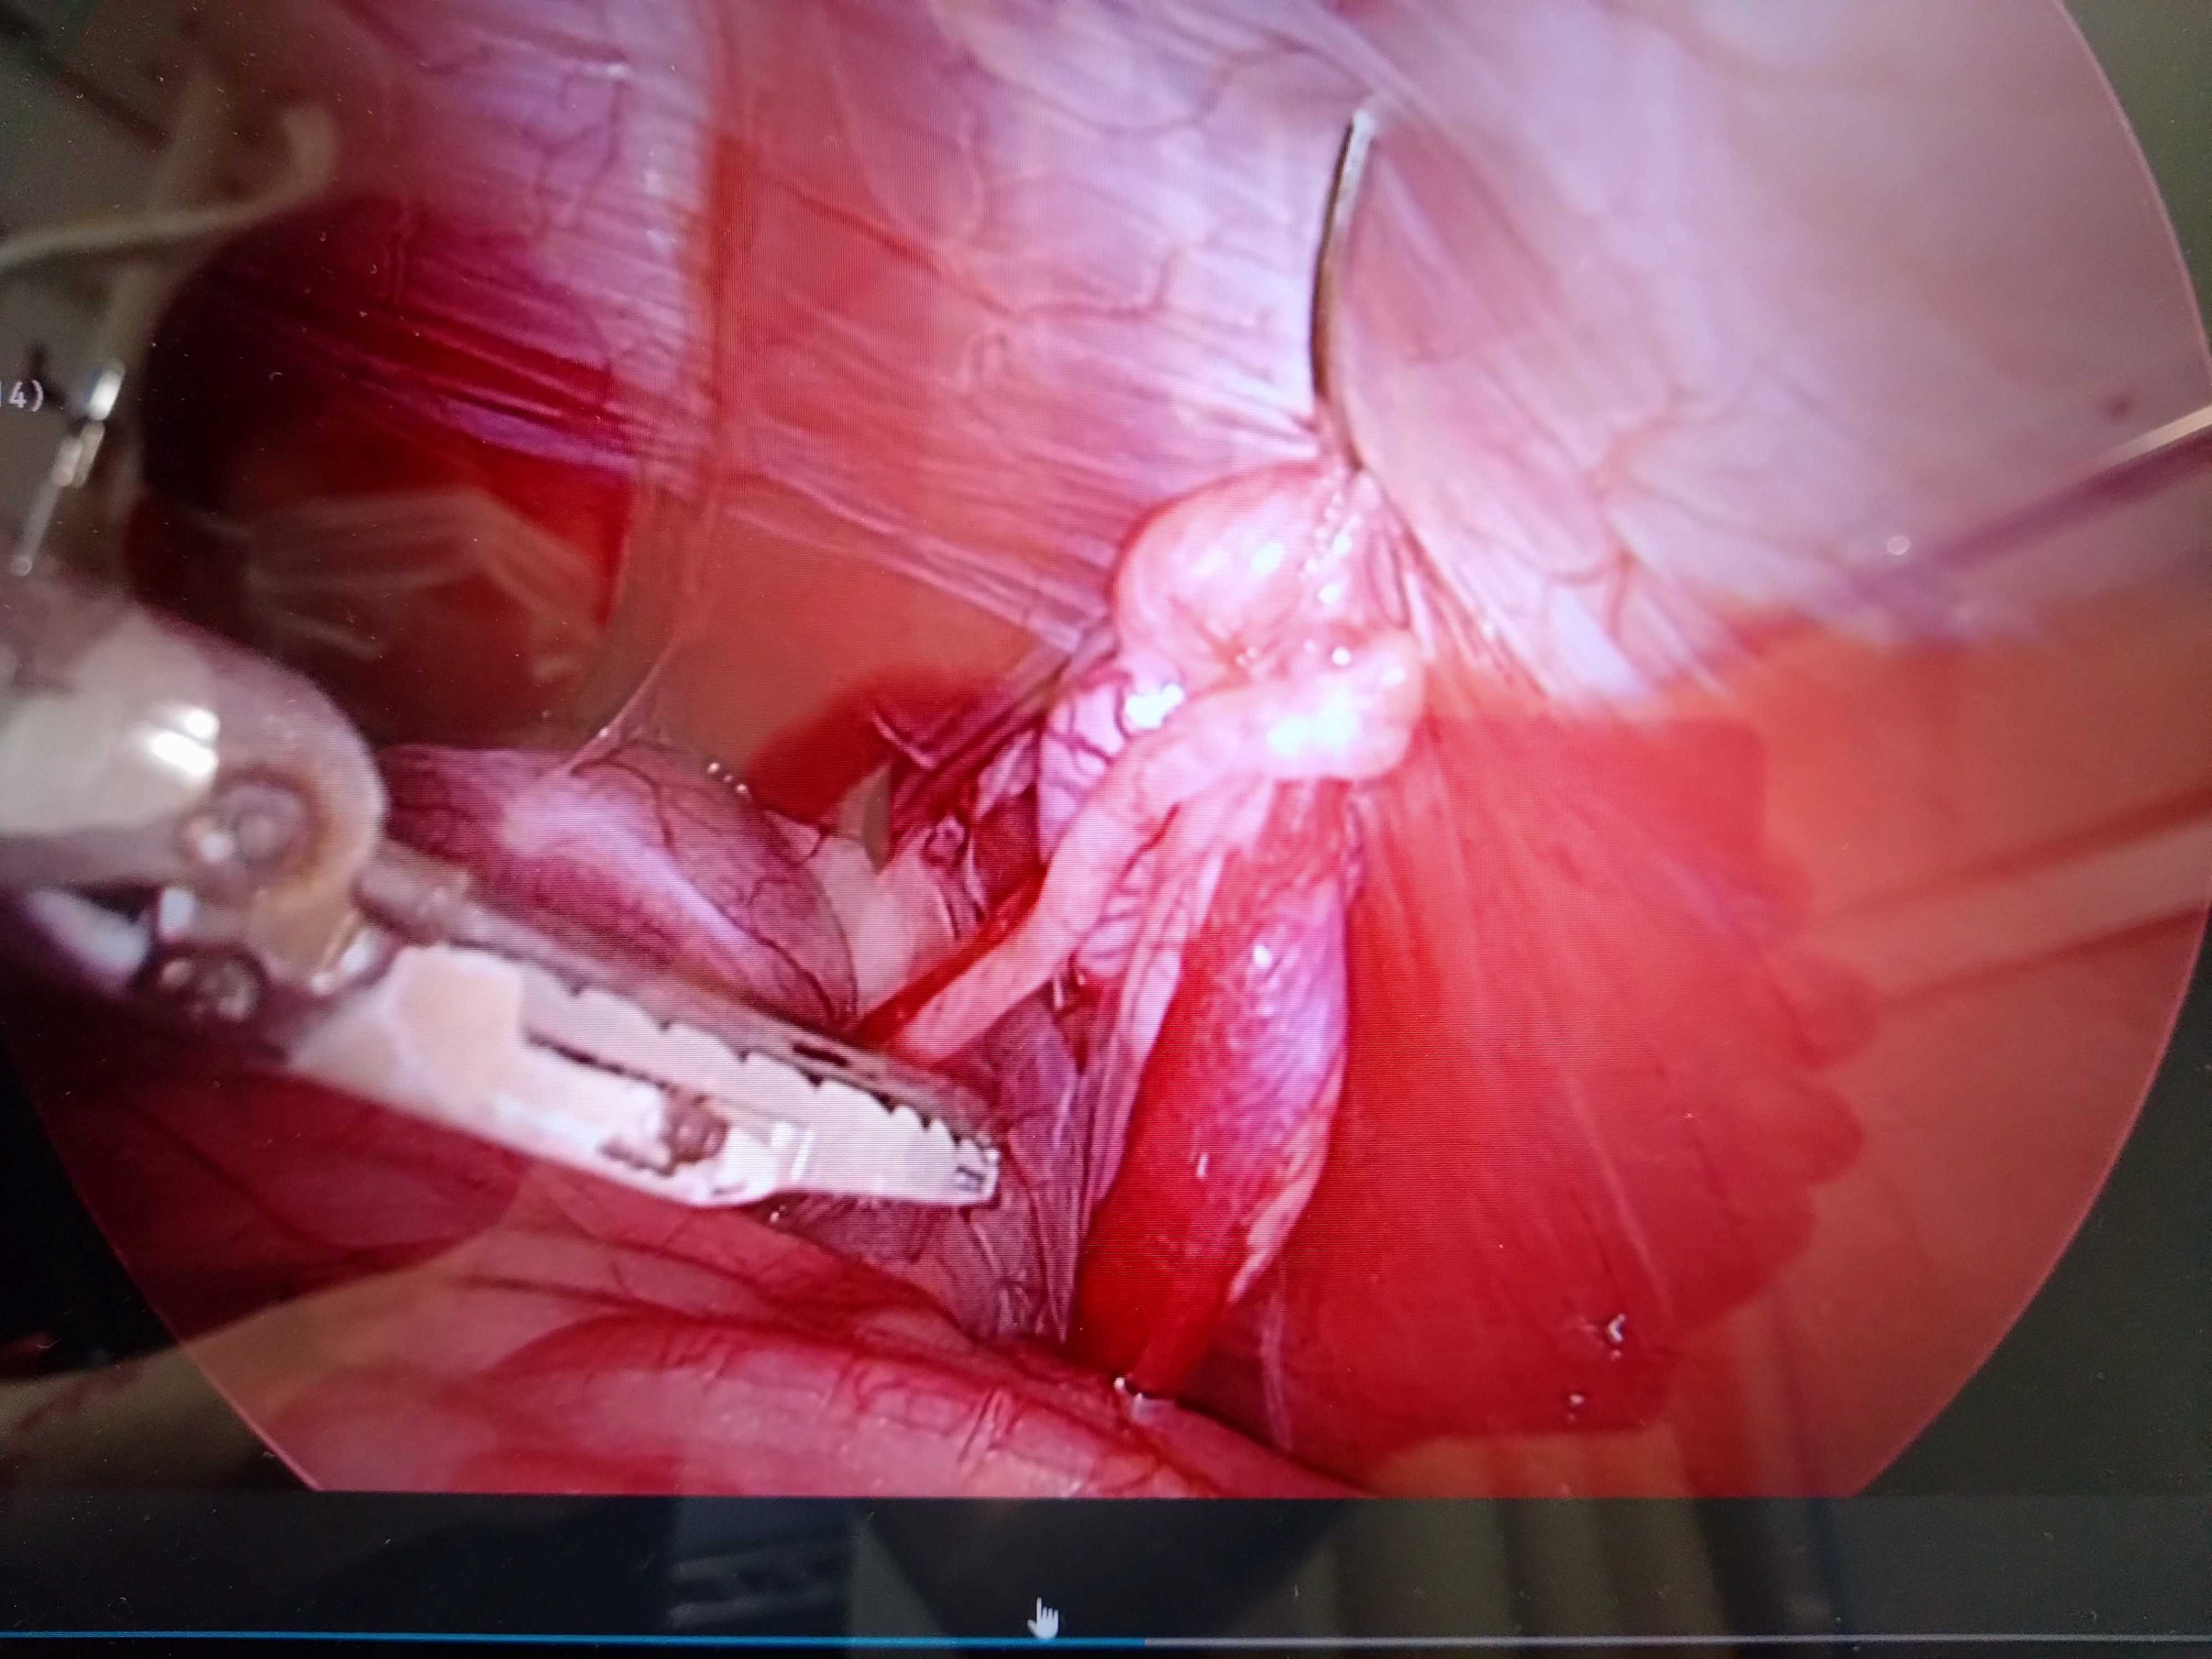

腹腔鏡下での犬の潜在精巣(陰睾)の摘出手術

これに対し、近年では腹腔鏡を使用した手技が確立し、開腹せず同様の手術を行うことが可能となっています。小さな傷で精巣を取り出すことができるため、開腹手術に比べて治りも早く、痛みがより少なく済むというメリットがあります。

腹腔内での精巣を持ち上げた様子

腹壁に吊り上げ針で固定して切除します